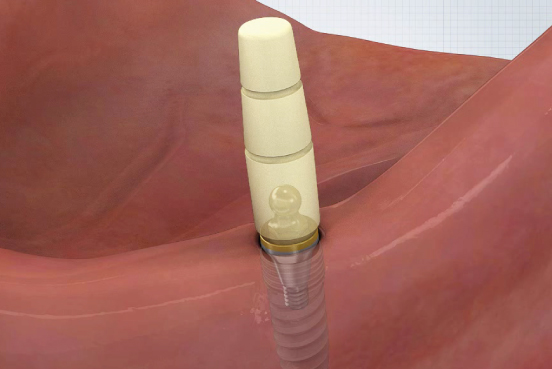

부분 상세설명 소모품교체 없음

소모품교체 없음Titanium housing과 Zirconia ball, Nitinol pan spring으로 이루어져 있어 소모품 교체 없이 장기간 사용이 가능하다.

Fixture 보호

Fixture 보호Locking 시 지대주와 housing 사이에 0.8mm 가량의 공간이 부여되어 의치 기능 시 연조직의 위축량을 보상함으로써 지대주에 가해지는 힘을 줄일 수 있다.

편측 20도 각도 보상

편측 20도 각도 보상지대주의 groove와 housing ball & spring이 체결되는 ‘EZ LOCKING 방식’에 의해 fixture의 식립각도를 20도까지 보상할 수 있다. (각도별 housing positioner 이용)